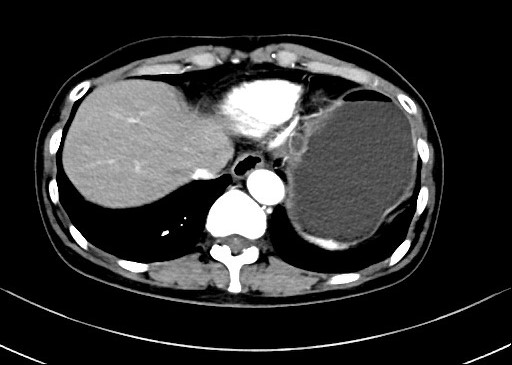

患者,66岁,女性,平素身体健康,以“发现胃肿物2年余”主诉入院,既往于外院行电子胃镜检查发现胃底隆起,直径约1.5-2.0cm,超声内镜检查考虑黏膜下来源间质瘤可能,不除外壁外病变压迫。外院CT提示胃底浆膜下囊性病变可能。患者及家属诊治心切,辗转数家医院后为求内镜下治疗遂来二附院。入院后在消化内科再次超声内镜检查,提示胃壁增生病变可能,增强CT提示胃底胃壁增厚,结合内镜检查。患者及家属强烈要求内镜下探查及病变切除术。术前在王进海主任的指导组织下,进行了专业组内及多学科讨论,与患者及家属充分沟通后,决定行内镜下切开探查及病变治疗术,必要时可行内镜-腹腔镜联合手术(LECS)。邹百仓教授带领内镜下肿瘤诊治及超级微创手术团队施行手术,术中逐层切开胃壁黏膜层及黏膜下层,暴露固有肌层,未发现胃壁病变,遂切开胃壁全层,局部腹腔探查,切口附近腹腔内似韧带组织上发现半球形隆起,表面透亮光滑,大小约1.5X1.5cm,术中请外科李军辉及袁庆攻教授会诊后确诊为囊性病变,讨论后建议可以观察或内镜切开引流,与患者家属沟通后家属强烈要求切开引流,遂用内镜切开刀切开囊肿,引流少量清亮囊液,囊肿塌瘪,观察囊肿切口及局部无出血,切除局部部分胃壁组织送检,内镜下严密关闭切口,留置胃管后,返回病房,常规对症治疗1周,患者无并发症发生,正常出院。

上腹部增强CT 超声内镜